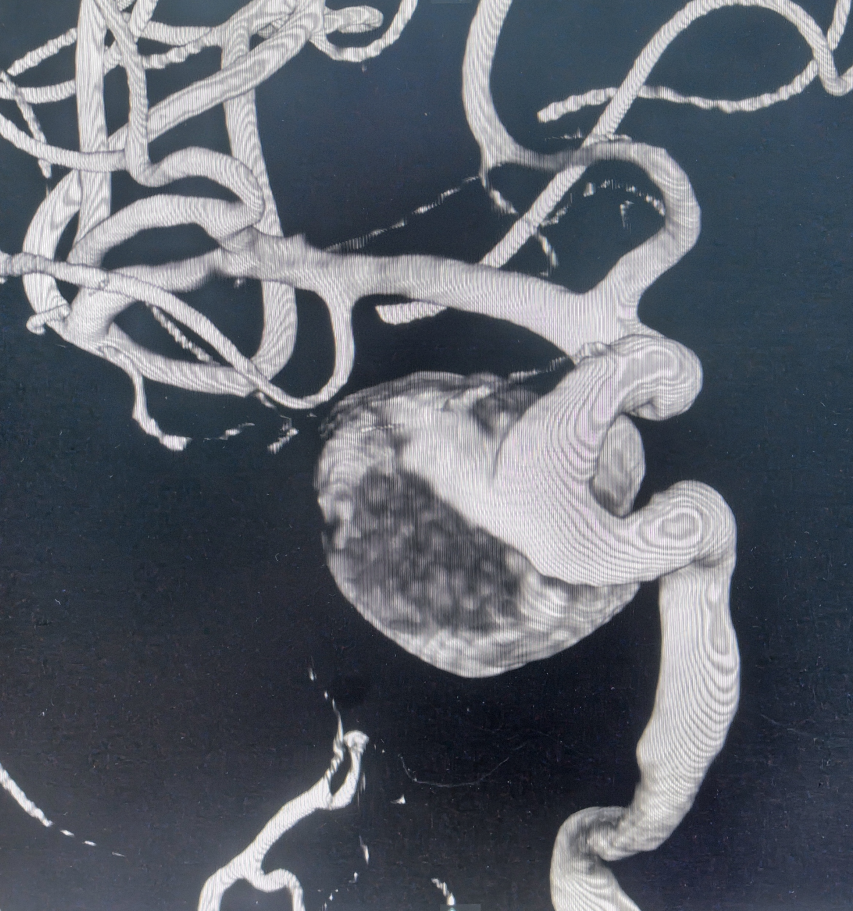

面对大动脉瘤且血管条件差的患者(腹主动脉S型迂曲,右侧颈总动脉II型牛角弓),以及颈内动脉多发动脉瘤的不同患者(C5-C7有5枚动脉瘤),吴全主任团队运用密网支架对症治疗,用一个支架巧妙解决大动脉瘤或多个动脉瘤难题,效果良好,患者短时间内快速恢复。